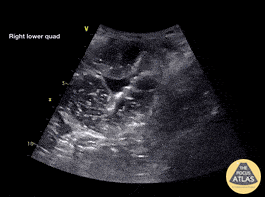

A 60 female presented with 3 days of vomiting, suprapubic distension and left groin pain. POCUS shows distended bowel loops (>2.5cm), 'to-and-fro' motion of hyperechoic bowel contents and extraluminal free fluid. NG was passed for decompression and surgical admission arranged. CT showed small bowel obstruction at the level of distal ileum within a left inguinal hernia Dr Cian McDermott, Mater University Hospital, Dublin, Ireland